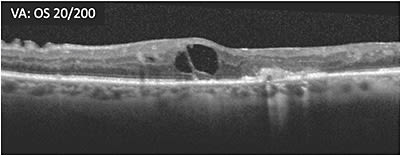

A 65-year-old male patient with proliferative diabetic retinopathy (PDR) who had undergone vitrectomy for nonclearing vitreous hemorrhage presented 2 months later. OCT showed substantial cystoid macular edema and hyperreflective foci (A) and he had poor vision (20/200 OS). The patient was started on treatment. Three months later, the retina was less swollen, but some macular edema remained, vision was 20/200, and cystic changes persisted (B). Treatment was switched within the same class in an effort to address the remaining macular edema. At 4 weeks following the initial treatment with the second therapy, vision remained poor (20/200 OS) and cystic spaces remained (C). Over the course of the next 8 months, the patient received 8 more treatments with the second therapy. Visual acuity was 20/100 -2 while the appearance of the cystic edema on OCT worsened (D).